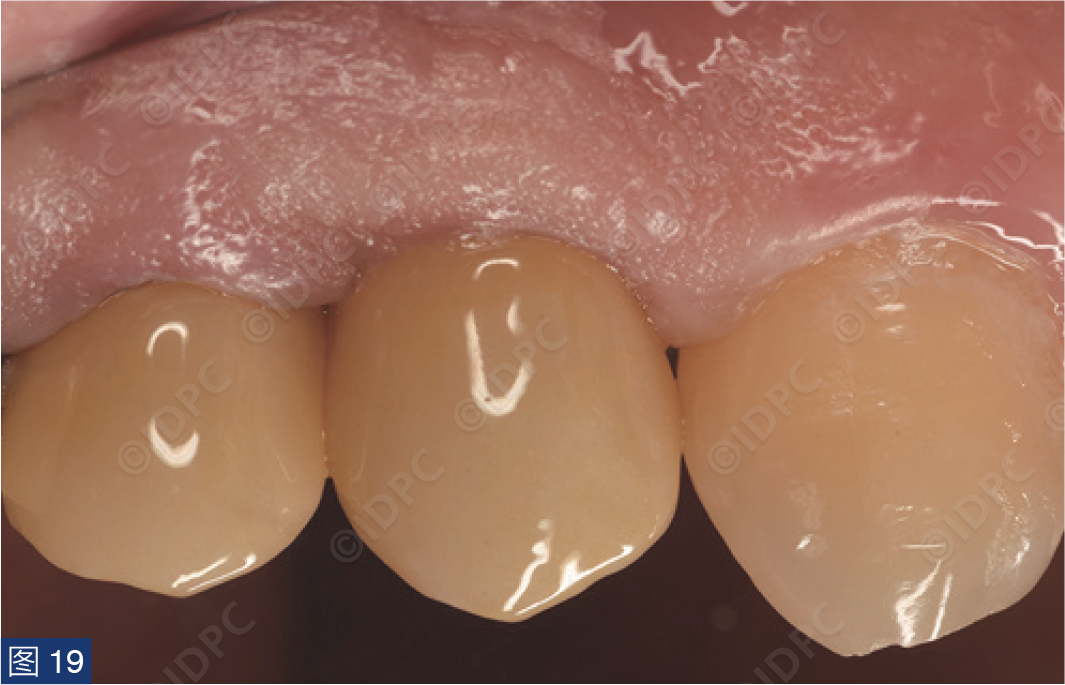

在exocad软件(exocad公司)上进行全数字化修复流程设计,在copaSKY uni.fit钛基底(bredent medical公司)上制作完成螺丝固位氧化锆混合陶瓷一体冠。种植位点显示出足够的颊侧软组织厚度(图12a)及良好的牙龈轮廓(图12b)。取下个性化愈合基台后,种植体周围软组织健康(图13、14),此外,取下后立即进行术前口内扫描以记录软组织轮廓。随后放置扫描体并进行数字印模以记录种植体位置(图15)。同时扫描对颌牙弓及咬合信息。获得的STL文件以数字方式发送至技工室。技工室在钛基底上完成聚甲基丙烯酸甲酯(PMMA)材料的试戴牙冠,以检查邻接和边缘密合情况,同时调整咬合(图16、17)。一旦完成所有调整,进行重新扫描。最终在钛基底上完成螺丝固位的全结构氧化锆混合陶瓷修复体,与牙龈接触的修复体表面高度抛光(图18),并以25 Ncm戴入口内。修复体实现了出色的颜色匹配及临床结果(图19)。螺丝孔用聚四氟乙烯填塞并用树脂材料密封(图20)。术后对照X线片显示修复体正确就位(图21)。六个月复查,增加的软组织轮廓清晰可见,牙槽骨水平保持稳定(图22-24)。

图19:最终修复体戴入后颊侧观,显示出完美的颜色及形态。